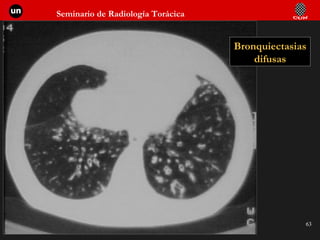

Bronquiectasias difusas

Definiciones “radiológicas” Asma: Episodios transitorios de obstrucción bronquial, con atrapamiento aéreo. Enfisema: Obstrucción bronquial crónica con atrapamiento aéreo y destrucción de parénquima. Bronquitis crónica: Episodios repetidos de inflamación bronquial con aumento de secreción. Bronquiectasias:  Dilataciones bronquiales que favorecen el acúmulo de moco.

Semiología de las bronquiectasias A A. Normal A. Normal B. Quistes de pared fina A. Normal B. Quistes de pared fina C. Quistes de pared gruesa A. Normal B. Quistes de pared fina C. Quistes de pared gruesa D. Ocupación parcial:  “Nidos de golondrina” A. Normal B. Quistes de pared fina C. Quistes de pared gruesa D. Ocupación parcial:  “Nidos de golondrina” E. Ocupación completa:  Nódulos B  C D E

Semiología de lasbronquiectasias A A. Normal A. Normal B. Quistes de pared fina A. Normal B. Quistes de pared fina C. Quistes de pared gruesa A. Normal B. Quistes de pared fina C. Quistes de pared gruesa D. Ocupación parcial: “Nidos de golondrina” A. Normal B. Quistes de pared fina C. Quistes de pared gruesa D. Ocupación parcial: “Nidos de golondrina” E. Ocupación completa: Nódulos B C D E